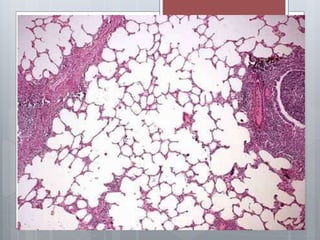

Pathological anatomy of chronic

diffuse obstructive emphysema

 Lungs increased in size, cover their edges

anterior mediastinum, swollen, pale, soft, do

not collapse, can be cut with a crunch.

 Of the bronchi, the walls of which are

thickened, squeezed muco-purulent

exudate.

 Bronchial mucosa full-blooded,

marked hypertrophy of the muscular

layer of uneven terminal bronchioles

and small bronchi, the appearance of

the mucosa of the last large number

of goblet cells.

 If the overall picture is dominated by changes in

the bronchioles, the expanded proximal acinar

(respiratory bronchioles 1st and 2nd order).

 This is called emphysema centeracinar.

 In the presence of inflammatory changes mainly

in the larger bronchi (eg, intralobular) bloating

and expansion affect the whole acinus and then

talk about panatsinarnoy emphysema.